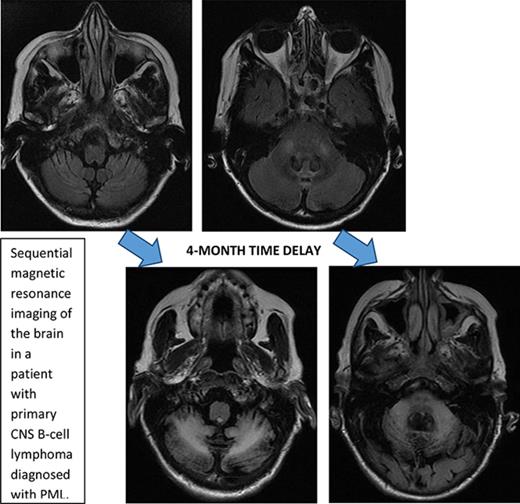

Initial symptoms included limb weakness (5 patients), visual loss (3 patients), cognitive impairment/behavior change (4 patients), and a cerebellar syndrome (4 patients). Magnetic resonance imaging abnormalities were restricted to the cerebrum in 12 patients; 2 patients had abnormalities restricted to the cerebellum and brainstem (Figure 1), and 2 patients had abnormalities in both the cerebrum and the brainstem and cerebellum.

Serial imaging of a patient diagnosed with CLL. Cancer-directed therapy included >6 months of rituximab and idelalisib. (A) Initial magnetic resonance imaging performed 2 months after the onset of headaches and balance disturbance (gait instability and repeated falls) depicting the asymmetric atrophy of the left cerebellum, which was not present in imaging performed 7 months earlier (not depicted). Fluid-attenuated inversion recovery (FLAIR) signal abnormalities are not present elsewhere. (B) Imaging repeated 3 months later (1 month prior to death) showing the continued atrophy of the left cerebellum with new confluent areas of FLAIR signal throughout the left cerebellum and left cerebellar peduncle without enhancement. Again, no FLAIR signal abnormalities are seen in the cerebrum.